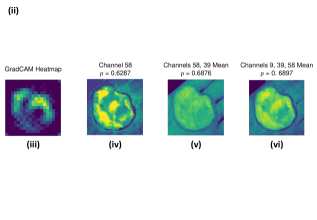

Figure 2a. illustrates the information retrieved from this CNN model from various layers of the architecture that is used to create a BAM map, which is used to segment the burn injury from normal skin in a 2D image. First, the heatmaps for the activations of the first convolutional layer are computed (Figure 2a(ii)), and then Grad-CAM heatmap is computed using the last convolutional layer (Figure 2a(iii)). Once the first convolutional layer heatmaps and Grad-CAM are generated, the algorithm uses a three-round iterative process to select activation heatmaps that have the highest correlation to the Grad-CAM heatmap among the channels of the first layer activations. After the process of correlating and selecting heatmaps is completed (Figure 3 ), segmentation masks are created next (Figure 4). A final composite BAM mask is created as illustrated in 2b(i). Finally, figure 2b (ii-iii) illustrates how the BAM mask is superimposed on the input image to segment the burn injury area, and how edge detection may be applied to the BAM mask in order to obtain a fine-tuned segmented boundary superimposed on the input image.

Figure 3 and Algorithm 1 detail the iterative process that is used to select the activation channel heatmaps and Grad-CAM, by the algorithm. For the example burn image, the first iteration of the algorithm selects channel since it has the highest correlation to the Grad-CAM heatmap among the channels of the first layer activations, as given by the Spearman’s correlation coefficient, . The second iteration selects channel to be added to the combination since averaging it with channel results in the highest increase in the correlation value with the Grad-CAM heatmap. Finally, the third iteration adds channel to the combination of channels and .